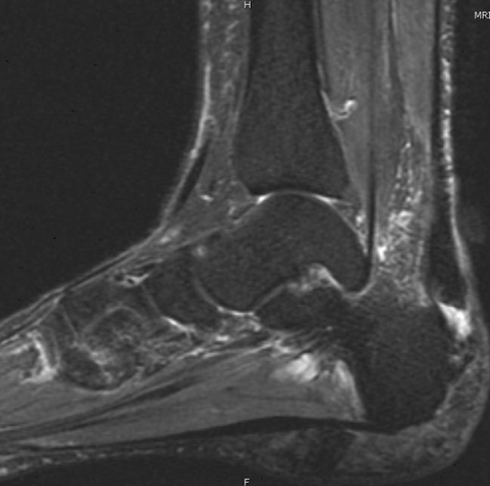

- Anatomy & Functional Biomechanics – Review of ankle and foot anatomy with MRI correlation, including tendons, ligaments, and key neurovascular structures relevant to clinical evaluation.